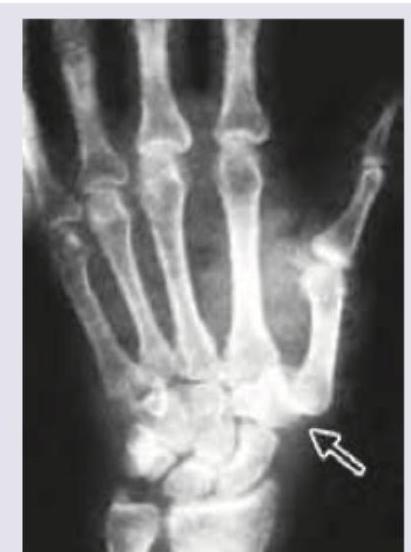

Explanation: ***Bennett fracture*** - The X-ray image shows an **intra-articular fracture** at the base of the **first metacarpal bone**, extending into the carpometacarpal (CMC) joint of the thumb. - This fracture is often **unstable** due to the pull of the abductor pollicis longus muscle, leading to dorsal and radial displacement of the metacarpal shaft. *Boxer fracture* - A Boxer fracture involves a break in the **neck of the fifth metacarpal bone**, typically occurring after punching a hard object. - While it is a common hand injury, the image clearly shows the fracture at the base of the thumb's metacarpal, not the fifth metacarpal. *Gamekeeper thumb* - Also known as skier's thumb, this injury is a tear or rupture of the **ulnar collateral ligament** of the metacarpophalangeal (MCP) joint of the thumb. - This condition is a soft tissue injury and would not typically present as a bone fracture on an X-ray, although avulsion fractures can sometimes be associated. *Colle's fracture* - A Colles' fracture is a fracture of the **distal radius** with dorsal displacement of the distal fragment, occurring about 1 inch proximal to the radiocarpal joint. - The fracture shown in the image is in the hand, specifically at the base of the thumb's metacarpal, and not in the distal forearm.

Explanation: ***A= Bennett fracture, B= Rolando fracture*** * **Bennett fracture** (A) is an **intra-articular fracture** of the base of the first metacarpal bone with a characteristic **two-part fracture** pattern. It involves a small fragment of the metacarpal base remaining attached to the carpometacarpal joint, while the rest of the metacarpal is dislocated. * **Rolando fracture** (B) is a **comminuted intra-articular fracture** at the base of the first metacarpal. It is characterized by a **Y or T-shaped fracture pattern**, indicating a more complex, three-part or more fragment involvement compared to a Bennett fracture. *A= Rolando fracture, B= Bennett fracture* * This option incorrectly identifies A as a Rolando fracture; Image A clearly shows a **two-part fracture** typical of a Bennett fracture, not the comminuted pattern of a Rolando. * Similarly, B is incorrectly identified as a Bennett fracture as it depicts a **multi-fragmented, Y-shaped fracture**, which defines a Rolando fracture. *A= Boxer's fracture, B= Bennett fracture* * **Boxer's fracture** is a fracture of the **neck of the fifth metacarpal**, which is not depicted in either image A or B. Both images show fractures at the base of the first metacarpal. * Image A is a **Bennett fracture**, not a Boxer's fracture, and B is a **Rolando fracture**, not a Bennett fracture. *A= Bennett fracture, B= Boxer's fracture* * While A is correctly identified as a **Bennett fracture**, B is incorrectly identified as a Boxer's fracture. * As previously stated, a **Boxer's fracture affects the fifth metacarpal**, whereas image B clearly shows a fracture of the first metacarpal base with multiple fragments.